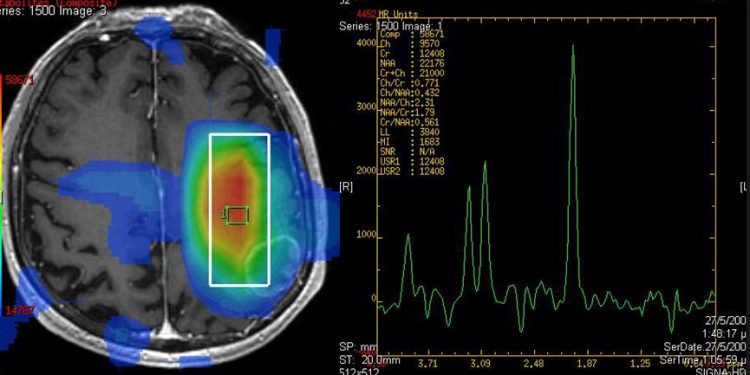

Мы утверждаем, что РС рецидивы в первую очередь вызваны метаболическими изменениями, влияющими на глиальную и нейронную функции, которые приводят к разрушению гематоэнцефалического барьера. Исследования протонной МР-спектроскопии подтвердили, что широко распространенная потеря нейронов присутствует даже в самом начале заболевания.

Данные МР-спектроскопии также свидетельствуют о том, что метаболизм нейронов дисфункция и потеря нейронов тесно связаны с прогрессированием заболевания и инвалидностью.